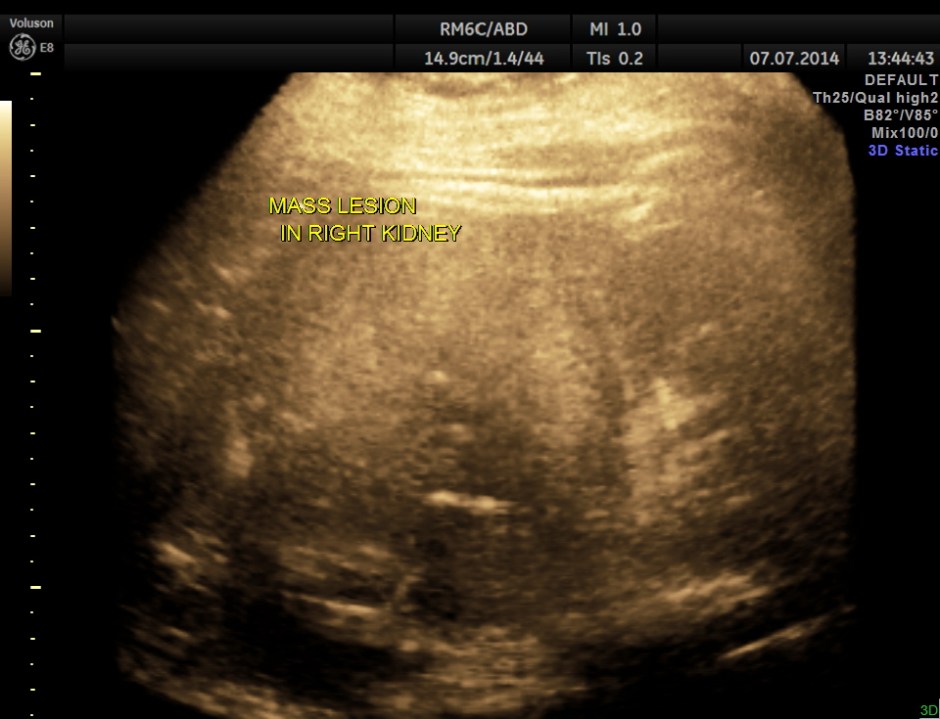

The right kidney is shown below. A solid mass is seen in the lower pole region.